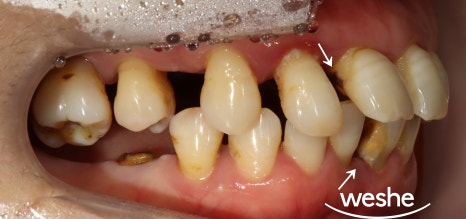

송정역 치과 치료 기간 : 2023.05.12~2024.02.14

특히 앞니 부위는

저작력이 집중되는 특성상

치주질환으로 인한 변화가

더욱 두드러지게 나타납니다.

치아가 앞쪽으로 밀려나거나

부채꼴 모양으로 벌어지는

현상이 대표적이며,

이러한 상황에서는 단순한

치주치료만으로는 근본적인

해결이 어려운 경우가 많습니다.

육안으로 확인되는 치아 간격의 정도와

잇몸의 염증 상태를 1차적으로 평가한 후,